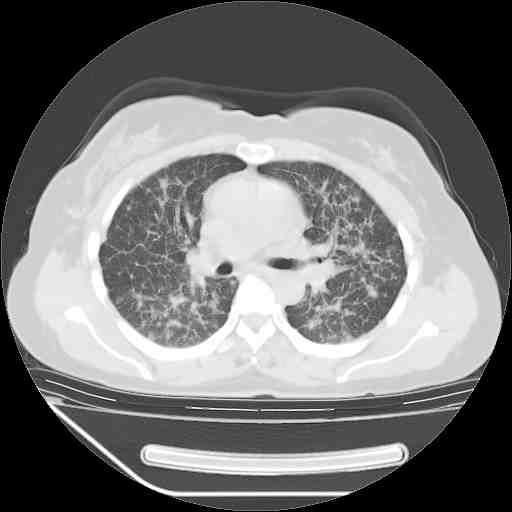

下面是今天刚刚做的,在上海治疗,吃了家属也说不清的一种药,一个月1万左右,

考虑  腺癌肺内转移,治疗较前病灶缩小、减少

肺癌并肺内转移,这种疾病治疗后在影像上看略有好转,不是很显著,但是肿瘤治疗效果影像只是一方面。

支持肺癌并肺内淋巴管炎,  原发灶小了,但转移较前片明显了.

支持右肺下叶周围型肺癌并肺内淋巴管炎,  原发灶小了,但转移较前片明显了.。

标准的细支气管肺泡癌呀!治疗后病情有所控制,也没治愈的迹象!

支持右肺下叶周围型肺癌并肺内淋巴管炎;病灶有所控制。